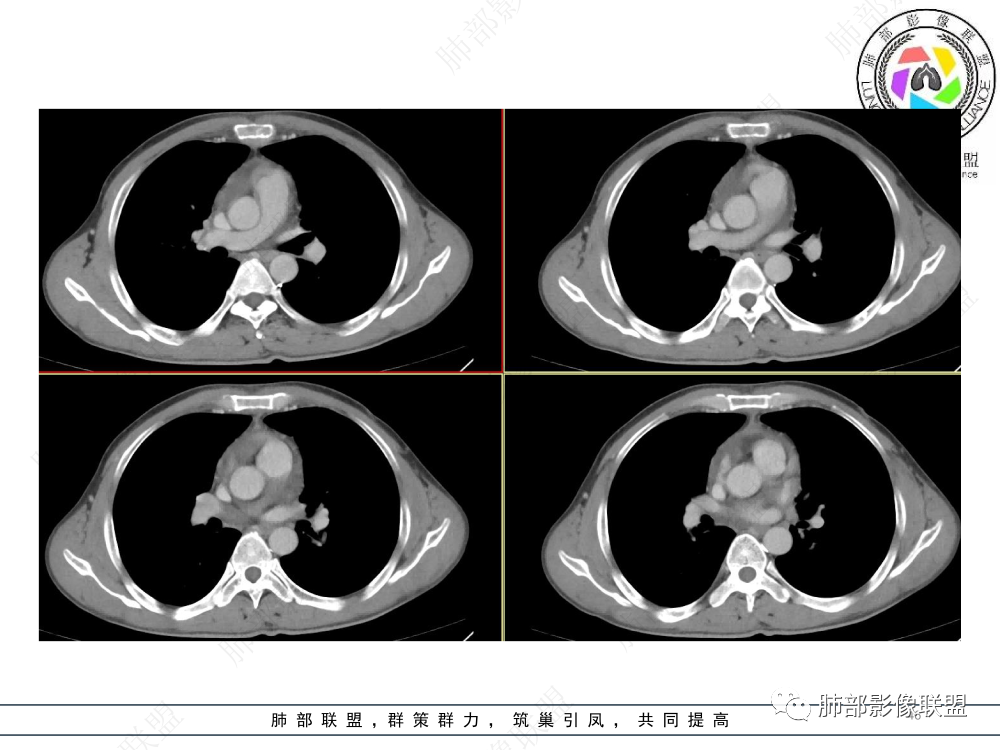

1.临床资料:中老年男性,病史较长-8个月,主诉胸痛,实验室资料:乳酸脱氢酶(LDH)升高。

2.影像表现:前上纵隔较大肿块,密度不均,形态不规则,边界不清,有结节样突起,脂肪间隙显示不清。病灶侵犯左无名静脉及上腔静脉,其中左无名静脉闭塞(胸背部侧支循环明显,亦表明回流受阻)。增强后轻中度不均强化。坏死边界欠清晰。可见心包积液,提示心包受侵犯。右侧上叶及纵隔胸膜下结节影,疑胸膜肺转移可能。胸骨柄后缘皮质不完整,疑骨质破坏(未提供骨窗及矢状位图像)。左锁骨上可见肿大淋巴结。